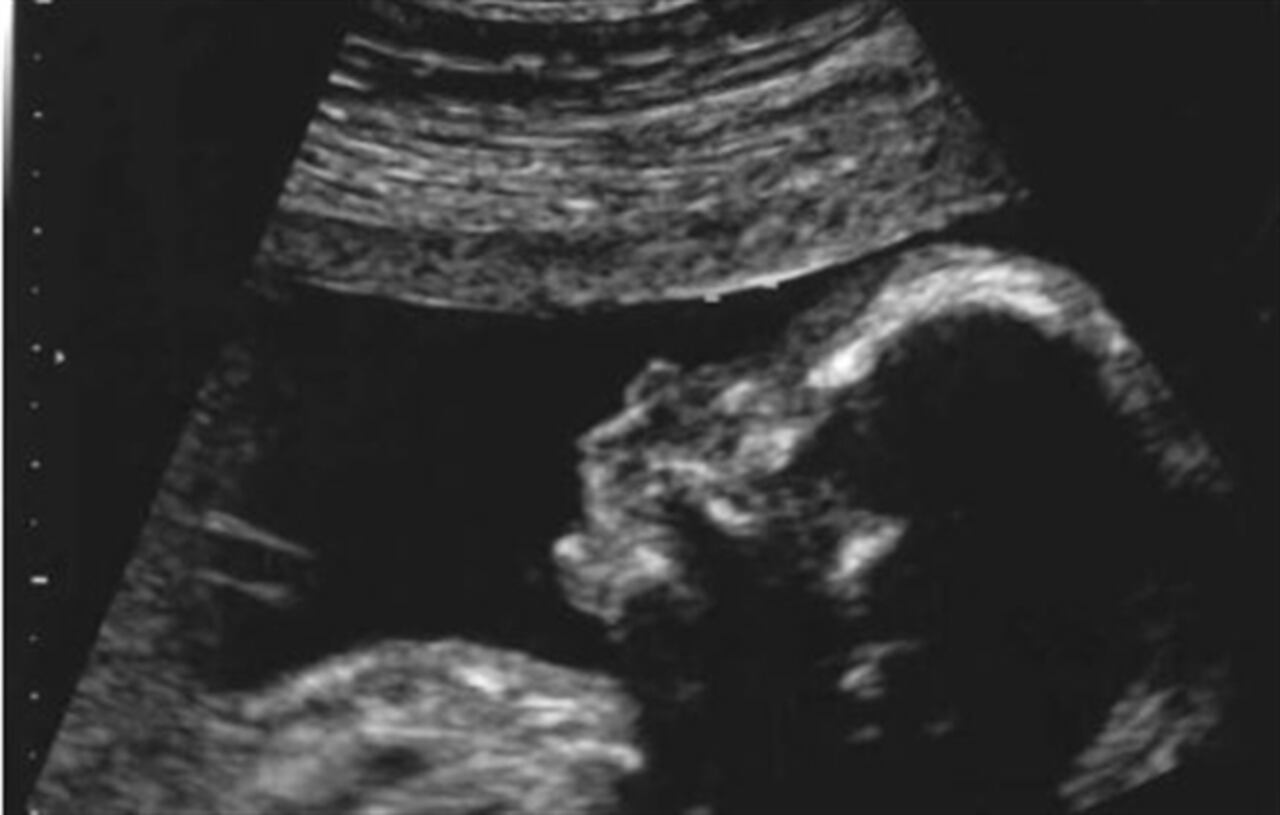

En esta etapa, una ecografía ayuda a evidenciar la presencia de los órganos genitales. Si se trata de un niño, este procedimiento ayudará a ver protuberancias correspondientes al pene y escroto. En cambio, cuando se notan unos labios, se sabrá es que será niña.

Como se mencionó anteriormente y tomando en cuenta la información de los expertos de Heathline en su artículo ‘Mitos versus hechos: señales de que vas a tener un bebé', se sabe que uno de los mejores métodos es la ecografía entre las semanas 18 y 22. Las señales para conocer el sexo del bebé son:

- Ausencia del pene: Si no hay presencia de bultos en la zona genital, queda descartado que sea hombre. Sin embargo, una segunda ecografía ayuda a confirmar la aparición del clítoris.

- Hamburguesa: Otra señal es esta, la cual corresponde a cuando aparecen tres líneas en la zona genital, haciendo referencia a los labios vaginales.

- Tortuga: Esta señal indica que el bebé será varón, debido a que la punta del pene se asoma detrás de los testículos del bebé.